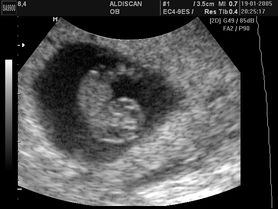

Płód w 6 tygodniu ciąży